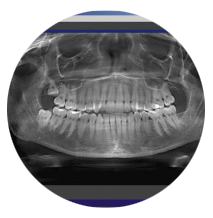

La lastra panoramica (ortopantomografia) che visualizza tutta la bocca e dà un quadro generale. Sebbene non sempre indispensabile, è consigliabile effettuarne una ogni qualche anno di controllo.

Lo studio effettua al suo interno anche le lastre panoramiche.